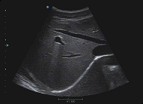

Medición automática IMT:El sistema ayuda automáticamente a medir el espesor de la Intima-Media de la pared de la arteria carótida a fin de evaluar las enfermedades cardiovasculares como la hipertensión por diabetes.